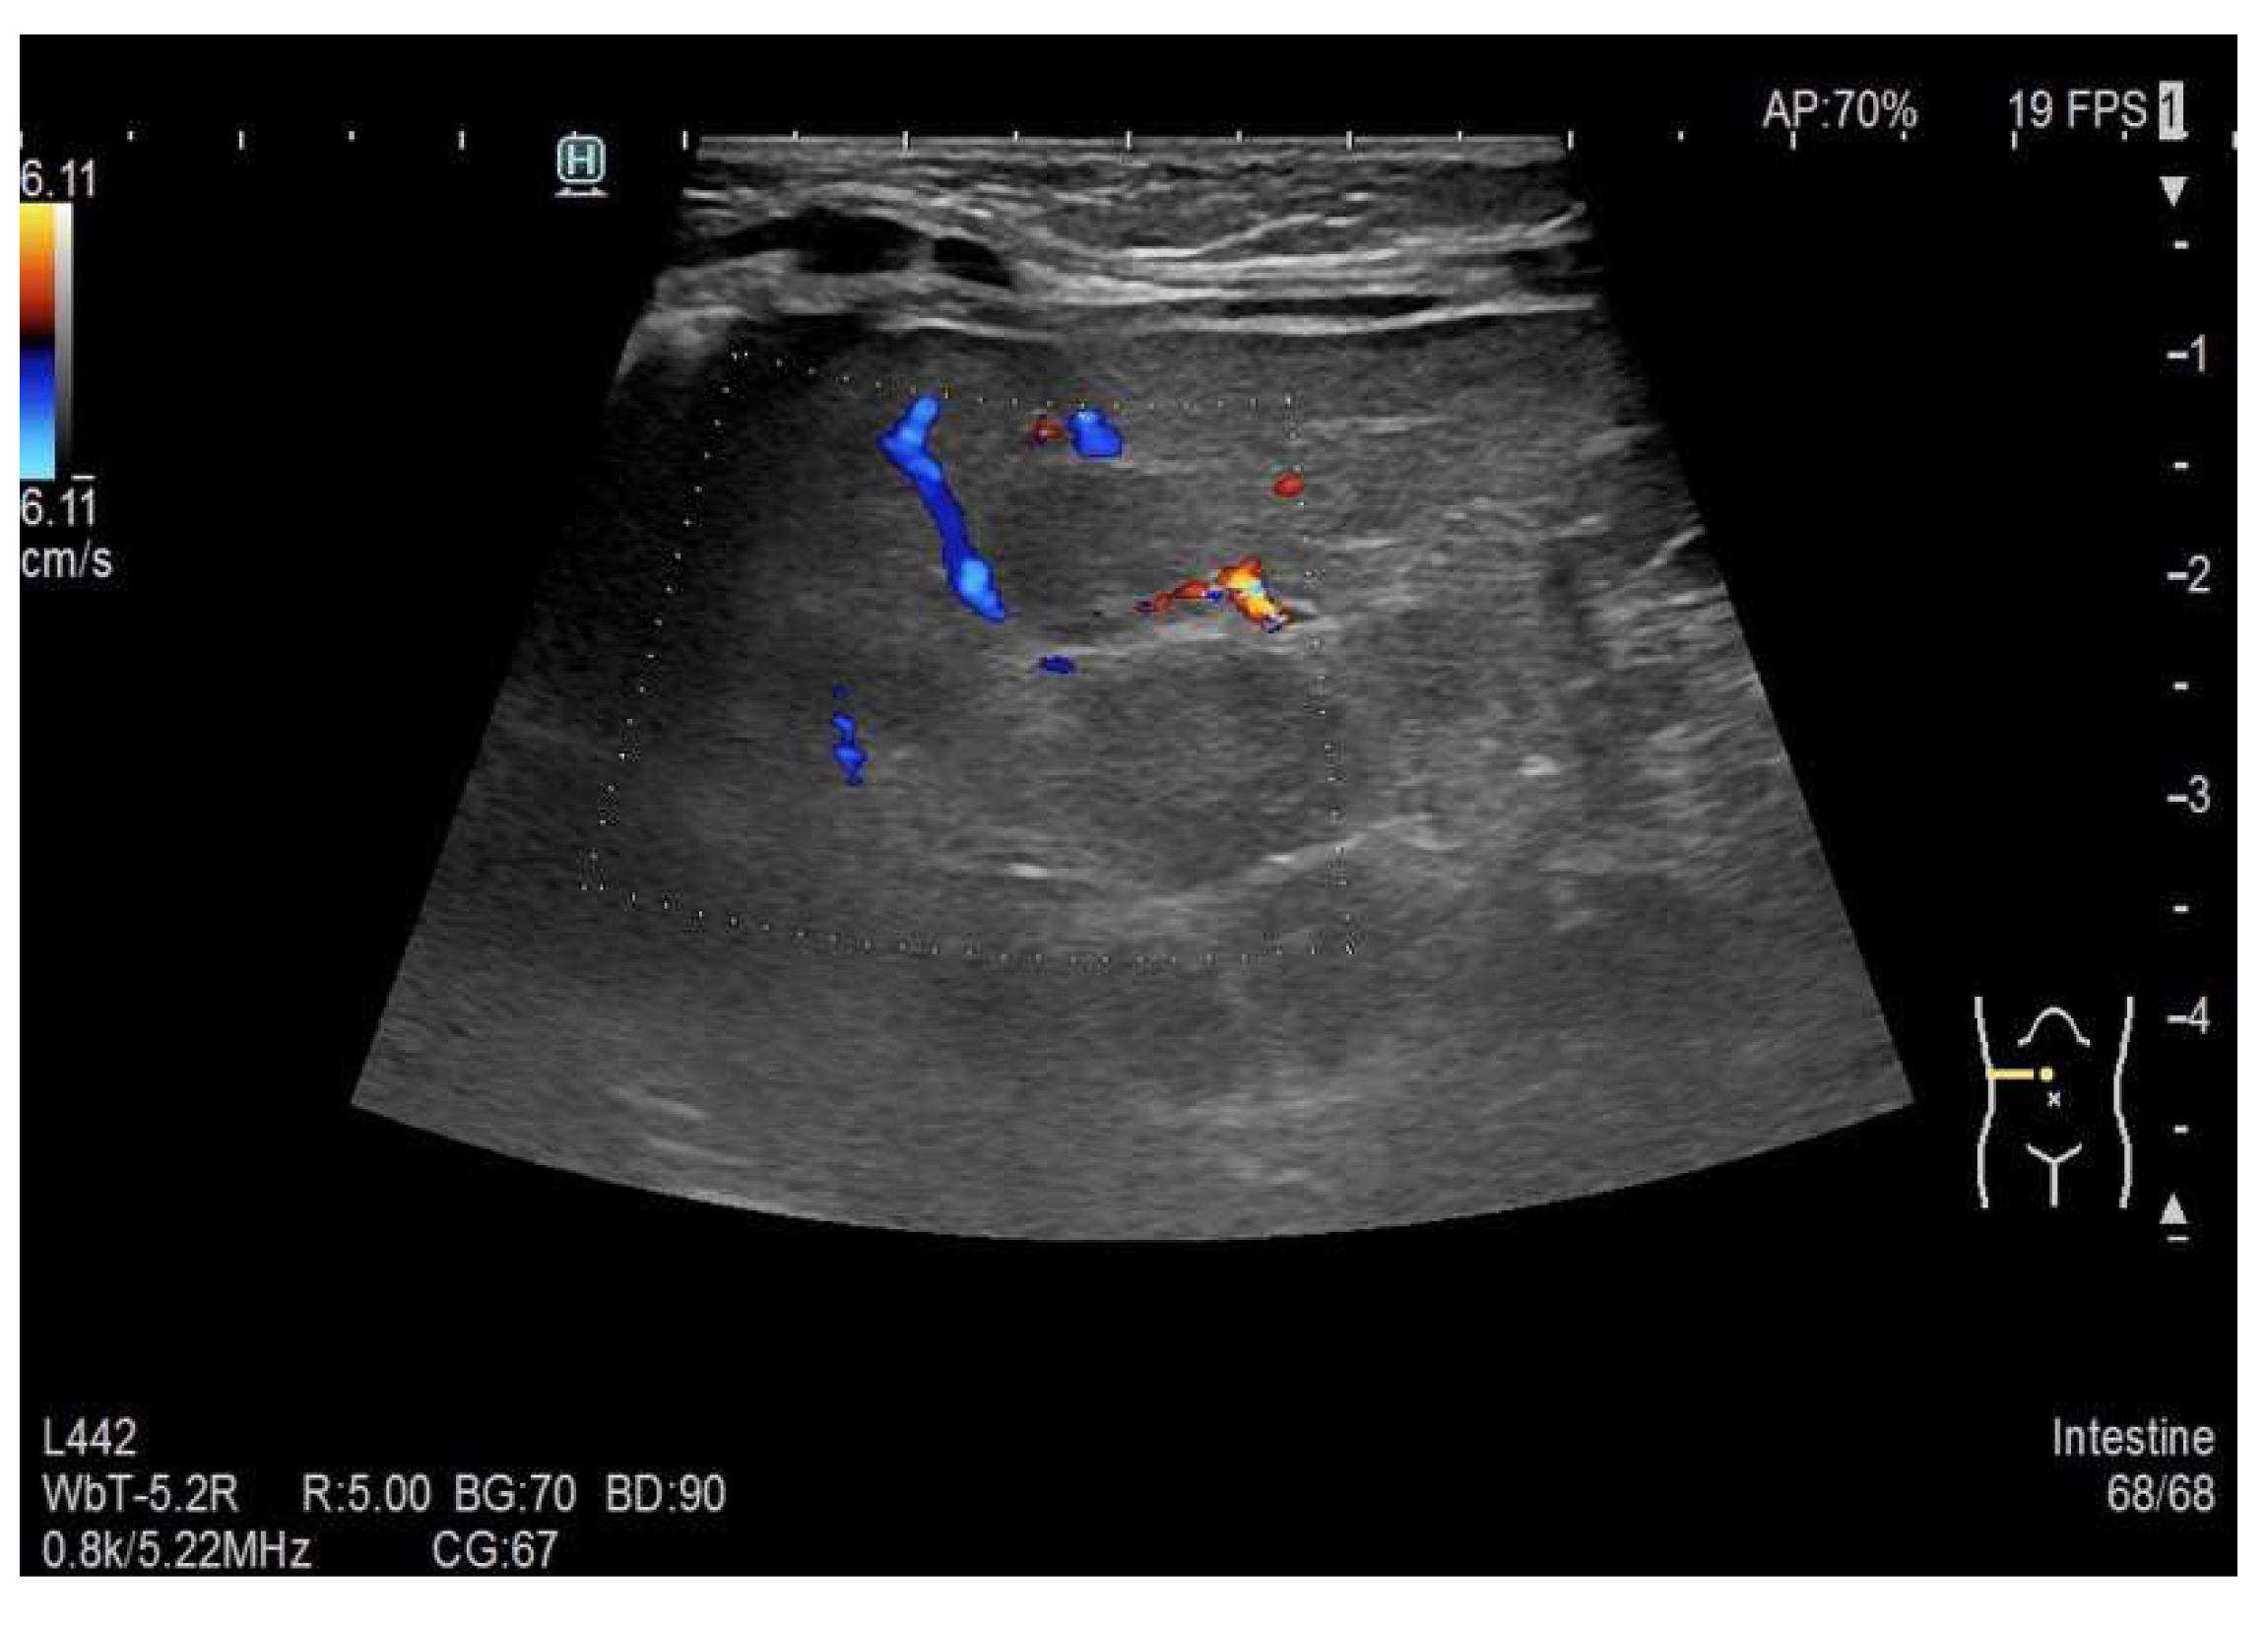

Preprints 73814 g002

Figure 4. Multiple hypoechoic liver lesions of up to approximately 12 mm in size.

Figure 5. Sparse peripheral vascularization of the lesions.